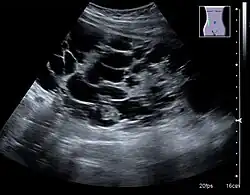

One of the primary indications for referral to US evaluation of the kidneys is evaluation of the urinary collecting system. Enlargement of the urinary collecting system is usually related to urinary obstruction and can include the pelvis, the calyces and the ureter. Hydronephrosis is seen as an anechoic fluid-filled interconnected space with enhancement within the renal sinus, and normally, the dilated pelvis can be differentiated from the dilated calyces.[1]

Figure 13. Hydronephrosis due to ureteropelvic junction obstruction in a pediatric patient.[1]

Several conditions can result in urinary obstruction. In both adults and children, masses, such as abscesses and tumors, can compress the ureter. In children, hydronephrosis can be caused by ureteropelvic junction obstruction, ectopic inserted ureter, primary megaureter and posterior urethral valve (Figure 13). In the latter, both kidneys will be affected. In adults, hydronephrosis can be caused by urolithiasis, obstructing the outlet of the renal pelvis or the ureter, and compression of the ureter from, e.g., pregnancy and retroperitoneal fibrosis. Urolithiasis is the most common cause of hydronephrosis in the adult patient and has a prevalence of 10%–15%.[1]